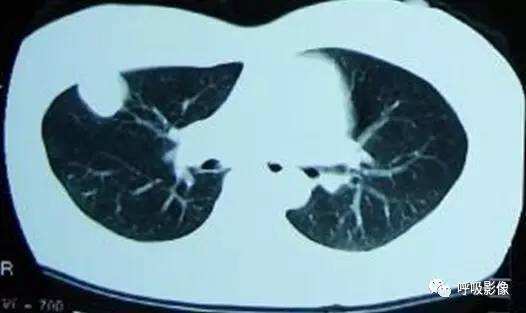

转移灶的影像早期 可表现为不规则的小片状影或磨玻璃样阴影,逐渐增密、增粗,形成边缘不光滑的结节或肿块影,可伴出血,此时边缘毛糙,周围出现晕征、铺路石征等(图2)。

图2 女,39岁 绒癌双肺转移伴肺内出血。可见肺内磨玻璃影典挤和铺路石征。